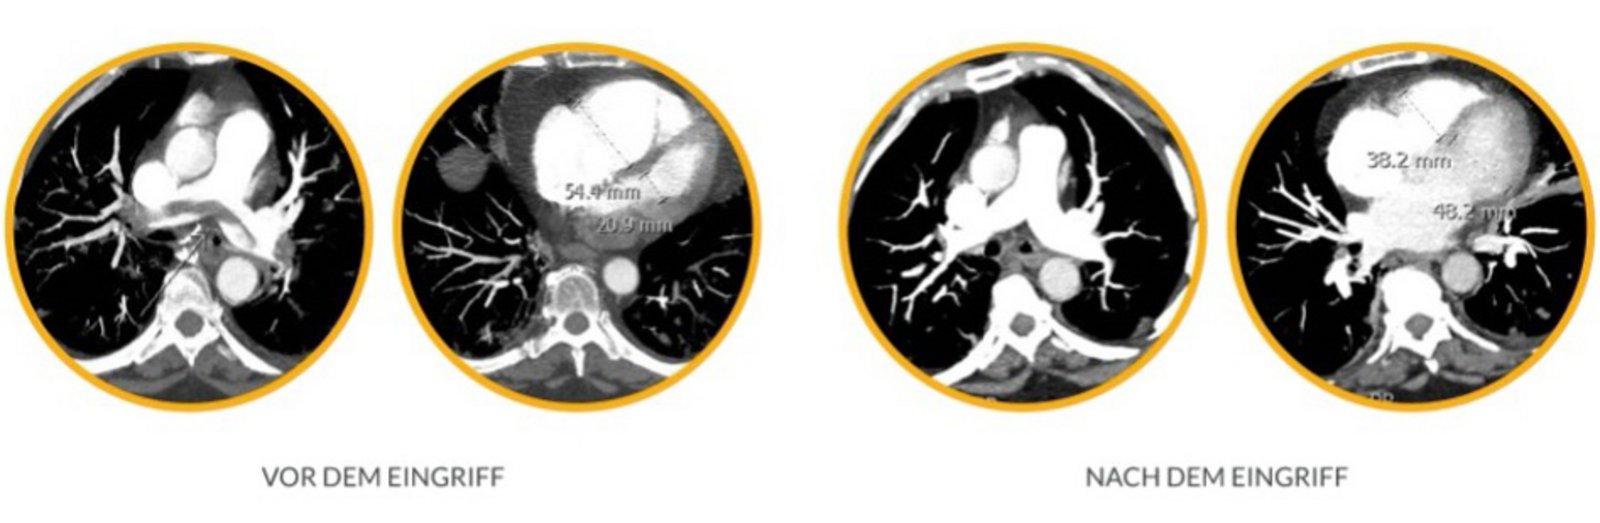

Durch die Entfernung großer, zentraler Thromben lässt sich eine sofortige Verbesserung der Hämodynamik und der klinischen Beschwerden erzielen.